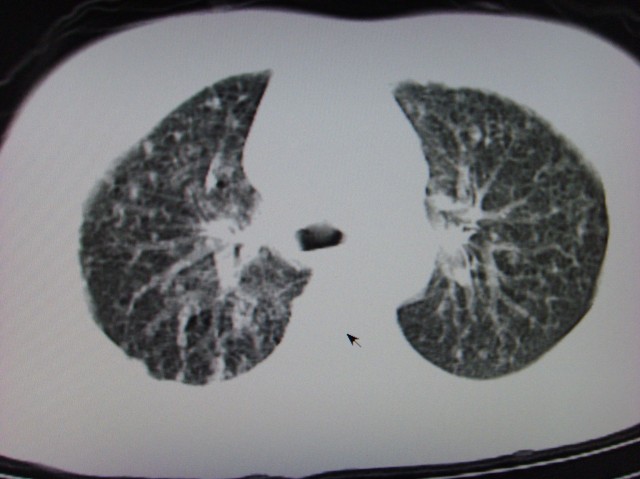

标题: CT7125:中央性肺Ca. [打印本页]

标题: CT7125:中央性肺Ca.

典型 中央型ca伴双肺、淋巴结转移

还有肺不张

典型 中央型ca伴双肺、淋巴结、胸膜转移

右下中心型肺癌伴双肺转移、纵隔淋巴结转移,癌性淋巴管炎可能性大

支持楼主的中央型肺癌,肺内,纵隔内淋巴结转移

典型的中央型ca伴双肺、纵隔淋巴结转移.

支持楼主诊断:中央型肺癌,肺内,纵隔内淋巴结转移。

典型--右下中心型肺癌伴双肺转移、纵隔淋巴结转移,癌性淋巴管炎可能性大

中心型肺癌伴双肺转移及纵隔淋巴结转移,癌性淋巴管炎

典型的中央型ca,肿快和肺门分界不清,肿快边界模糊,呈毛刺状。伴淋巴结转移。

首先考虑中央型肺癌伴阻塞性肺炎双肺、淋巴结转移,可以正规抗炎治疗一周后复查